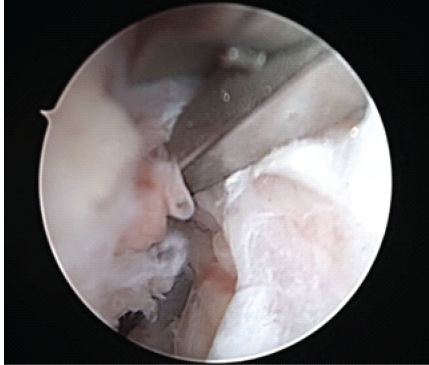

The medial meniscus was stable to probing, and photographs taken. Next, the patient had attention directed toward the lateral meniscus. The lateral meniscus was unremarkable and stable to probing, with photographs taken. Next, an arthrex passport was placed in the anteromedial portal. The knee scorpion was used to pass arthrex fiberloop suture through the tibial stump. With traction on the suture in the tibial stump, there was improved access and visualization to the femoral stump. Attempts at passing suture through the femoral stump with the arthrex knee scorpion were unsuccessful as the instrument was too large to gain access to the proximal femoral stump with the constraints of the small intercondylar notch. The arthrex labral repair scorpion was utilized as it was smaller, had a larger depth of bite, and was able to gain access to the intercondylar notch for secure fixation onto the femoral stump (Figs. 2, 3, 4, 5).

Figure 2: Intraoperative arthroscopic image of the right knee taken from the anterolateral viewing portal of Arthrex Labral Scorpion brought in from the anteromedial portal passing suture within the proximal femoral stump.

The arthrex labral scorpion is a straightforward, easy-to-use tool utilizing a narrower and more pointed tip (Fig. 4) to facilitate the surgeon’s ability to grasp, pierce, and pass suture for precise placement and anatomic repair during ACL repair (Fig. 2) when another suture passer, such as the arthrex knee scorpion, is of improper size or not available. This knowledge greatly assists the surgeon in anatomic repair and stabilization, and allows the surgeon to complete the operation when there is limited instrumentation, or the surgeon needs an instrument with a lower profile to gain access for soft-tissue repair in tight spaces as in our case. Perhaps, mid-substance ACL repair outcomes will be improved by the ability to get better fixation with suture purchase in the proximal stump. Although there have been many techniques described to accomplish ACL repair, there is consensus that the location of the tear, tissue quality, proper suture placement, and fixation techniques during repair of ACL tears are all important factors to achieve an optimal outcome with a lower incidence of retear [9,10,11,12]. Our patient’s family chose ACL repair after extensive discussion regarding the risks and benefits of various forms of treatment, both non-operative and operative, including ACL reconstruction. The patient and family requested to avoid the associated risk of knee pain and physeal injury associated with ACL reconstruction, which was a recommended procedure to them, due to the family history of both biological parents having undergone ACL reconstruction, and understanding the extensive post-operative therapy protocol and recovery. When evaluating ACL repair versus ACL reconstruction, evidence suggests that both ACL repair and ACL reconstruction are appropriate treatments, though ACL reconstruction shows lower rates of rerupture [4,9]. However, ACL repair may avoid physeal injury and knee pain and has the potential advantages of reduced surgical trauma, avoidance of autograft harvest complications, and maintaining native ACL tissue proprioceptive function [9,10]. One of the most feared and devastating complications of ACL reconstruction in the pediatric populations, which is felt to be underreported, is damage to the physis that can lead either to a growth arrest resulting in a limb length discrepancy or an angular deformity [1,2,3,4,9]. In retrospect, ACL repair was the ideal fixation method for this patient in view of premenstrual status with open growth plates to avoid physeal injury and the family’s desire to avoid a more major surgery and harvest site morbidity. Although ACL repair particularly for mid substance tears has shown higher retear rates compared to ACL reconstruction [4,9], in recent years, there have been many studies demonstrating that ACL repair is a safe and effective method of managing such injuries in the pediatric patient while avoiding some of the complications associated with conventional ACL reconstructive techniques [9,10,11,12]. Certainly, in our case, there was extensive planning and communication before surgery with the instrumentation representatives, OR director, and operating team to ensure all necessary equipment was available to accomplish ACL repair and fixation in a timely manner to minimize OR time and surgical risks. ACL repair has been shown to be beneficial for the treatment of ACL rupture in the pediatric population with reduced surgical morbidity [9,10,11,12]. Despite our planning, the intercondylar distance did not accommodate the thickness of the arthrex knee scorpion. Fortunately, being cross trained and having the knowledge of the arthrex labral scorpion provided an easy to administer solution to successfully place suture in the femoral stump to accommodate ACL repair and stabilization which can accommodate a variety of different ACL tear locations and shapes, difference in sizes of the femoral stump, or in our case limited space secondary to a child with smaller bones and narrower intercondylar distance.